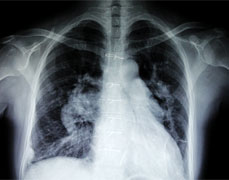

近日,瑞康医院胸心外科联合神经内科、耳鼻喉等多科协作,成功为一名重症肌无力患者实施了胸腺瘤切除术+前纵隔脂肪清扫术。 终于摆脱了浑身...